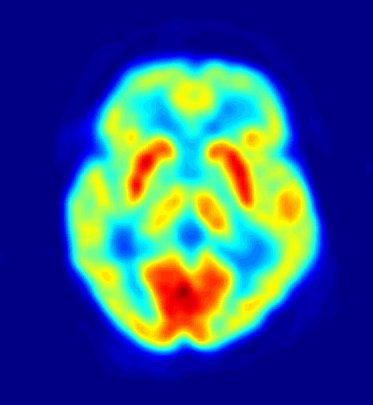

Así, procesando toda la información que reciben los anillos que rodean a la persona mediante un ordenador, pueden localizarse muchos de los átomos inestables originales según se van desintegrando. Cuantos más positrones hayan sido emitidos en un lugar determinado (es decir, cuantos más pares de fotones hayan definido líneas rectas que se corten en ese lugar) más cantidad de sustancia marcadora ha sido absorbida por esas células. Al final se representa la intensidad de emisión de positrones en cada punto con una gradación de colores, como en este ejemplo de una TEP del cerebro:

La emisión de positrones es mínima en el color azul y máxima en el color rojo. Puedes ver que el objeto de una TEP no es tanto “ver” el interior del cuerpo –para eso suele usarse una Tomografía Axial Computarizada (TAC), aunque de eso hablaremos en alguna otra entrada, si ésta no os aburre soberanamente–, sino para detectar qué zonas del cuerpo absorben determinados compuestos.

Por ejemplo, he mencionado antes que las células cancerosas consumen glucosa, normalmente, a mayor velocidad que las normales, de modo que se utilizan estas tomografías para pacientes con la enfermedad de Hodgkin, otros linfomas, cánceres de pulmón, etc. De hecho, el 90% de las TEPtienen que ver con la oncología. Pero no es el único asunto en el que son útiles: puesto que las células activas consumen más glucosa que las que no lo están tanto (o están muertas), se utiliza también para ayudar en el diagnóstico de la enfermedad de Alzheimer: el consumo de glucosa permite realizar un mapa del consumo de sangre en el cerebro.